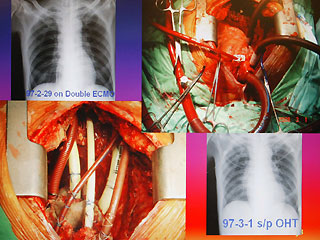

報(bào)道說,現(xiàn)年60歲的陳先生,2月初因發(fā)現(xiàn)感染細(xì)菌性心內(nèi)膜炎,致使整顆心臟感染嚴(yán)重,從奇美醫(yī)院轉(zhuǎn)到臺(tái)大醫(yī)院之后,經(jīng)家屬同意,決定進(jìn)行全心臟摘除,然后置入葉克膜維持生命。陳先生最后靠著葉克膜撐過16天,奇跡式活下來(lái),于今天順利出院。

臺(tái)大醫(yī)院心臟血管外科教授王水深率領(lǐng)團(tuán)隊(duì)執(zhí)行這個(gè)艱難的手術(shù)。他說,陳先生心臟的三尖瓣膜等處已被細(xì)菌噬光,無(wú)法修補(bǔ),最后“走投無(wú)路”之下,決定先摘除心臟,而家屬的決定也需要相當(dāng)大的勇氣。

王水深說,摘除心臟時(shí)沒人能保證有心臟可換,而靠葉克膜體外維生系統(tǒng)通常也只能維持7天左右,但陳先生靠著兩套葉克膜奇跡式的撐過16天,克服感染及排斥,又能幸運(yùn)的等到心臟捐贈(zèng)者,他強(qiáng)調(diào),翻遍文獻(xiàn)可說史無(wú)前例。(周先)